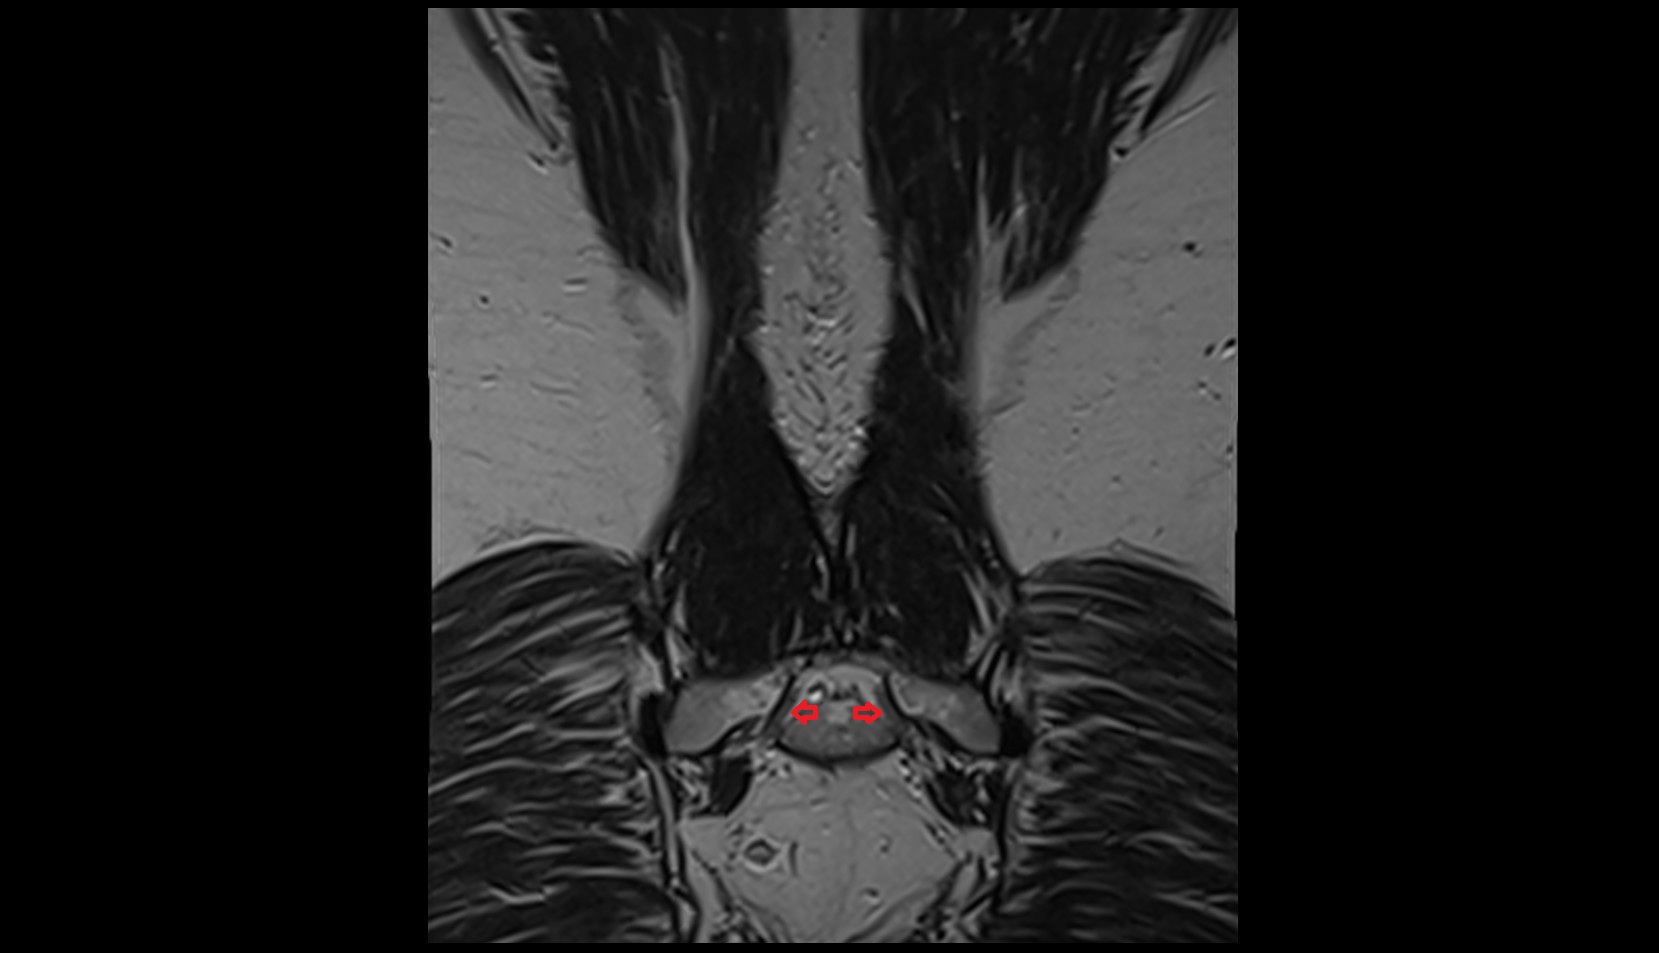

- Peripheral zone of prostate

- Anterior Fibromuscular Stroma of prostate

- Central zone of prostate

- Transitional zone of prostate